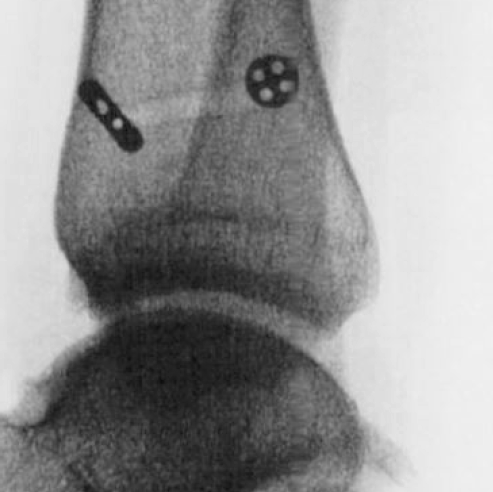

The two bones of the leg (tibia and fibula) are connected just above the ankle by strong ligaments. This connection is called the ankle syndesmosis. It allows a small amount of movement between the leg bones during activities.

See images below

Weight-bearing X-rays comparing both ankles are useful, with MRI, weight-bearing CT and even ankle arthroscopy sometimes required to determine whether the syndesmosis is stable or unstable (see images below).